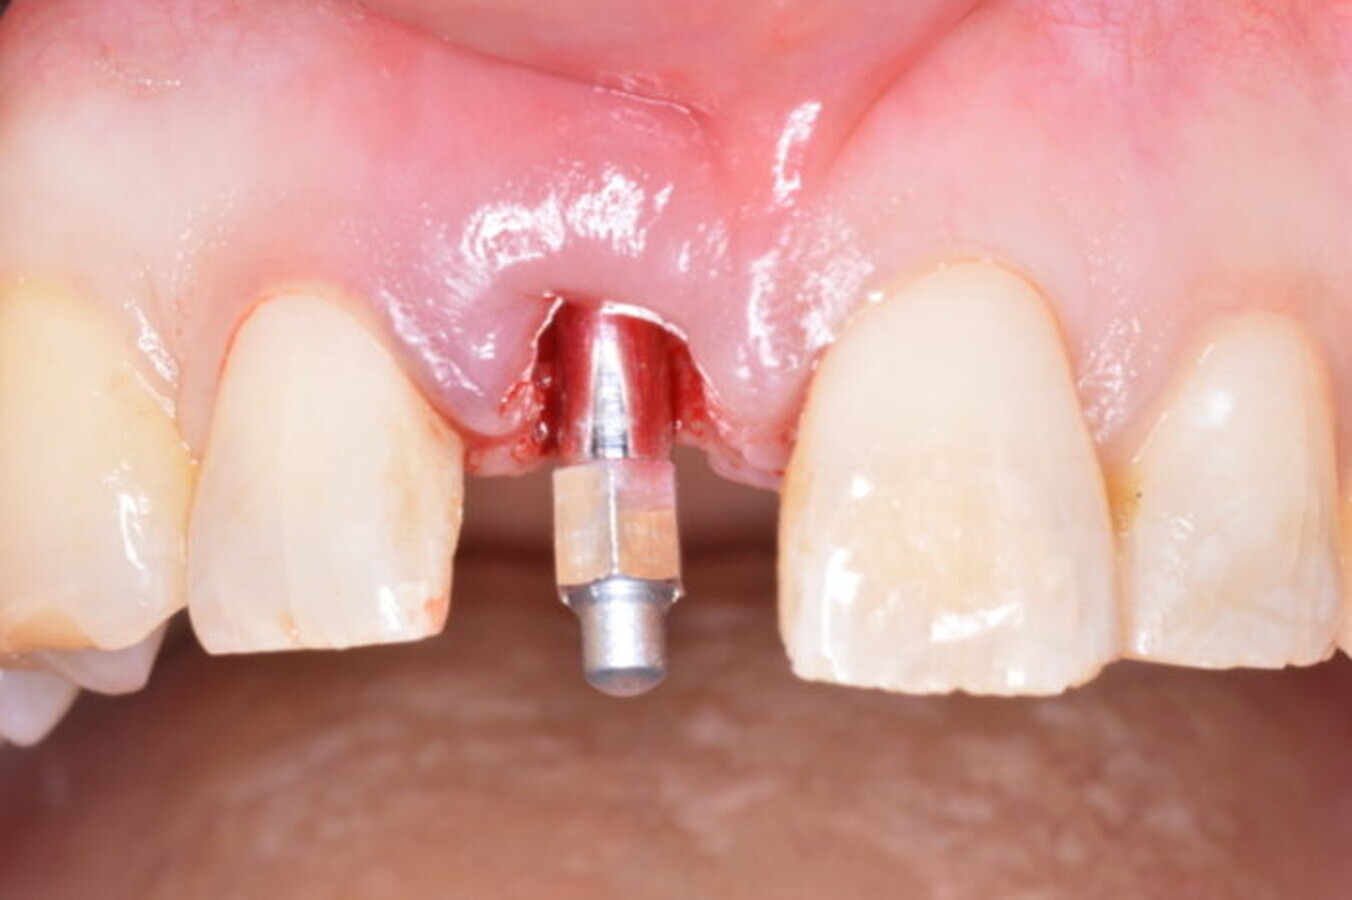

SmartPeg attached in order to record ISQ for an immediate implant replacing tooth #11 prior to immediate temporisation. (Image: Barry P. Levin)

Immediate implant placement for tooth #13 after extraction. It was followed by immediate provisionalisation. (Image: Barry P. Levin)

What are the main learning objectives for the viewers of your webinar? Viewers will learn the value of recording ITV and ISQ measurements at the time of implant placement and how to apply these values with regard to loading protocols. I will also discuss possible negative effects on crestal bone if an excessively high ITV is required to fully seat an implant in healed or grafted sites. In addition, I will highlight the importance of recording ISQ values not only at the time of implant placement but also at follow-up periods to monitor and confirm secondary stability.